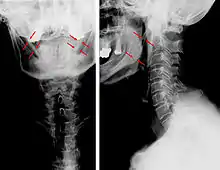

Anteroposterior and lateral radiographs of cervical spine showing ossification of the stylohyoid ligament on both sides

Imaging is important and is diagnostic. Visualizing the styloid process on a CT scan with 3D reconstruction is the suggested imaging technique.[12] The enlarged styloid may be visible on an orthopantogram or a lateral soft tissue X ray of the neck.